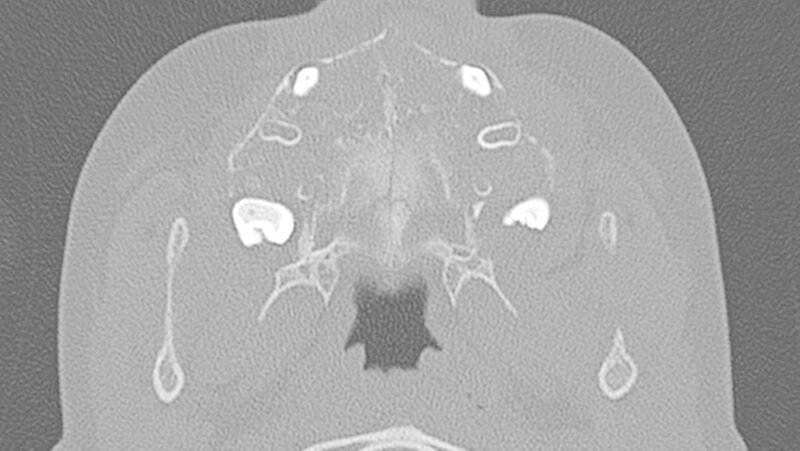

Da die konventionelle Röntgenuntersuchung keinen wegweisenden Befund zeigte, wurde die bildgebende Diagnostik um eine Dünnschicht-Computertomografie (HR-CT) des Mittelgesichts, eine Magnetresonanztomografie (MRT) des Kopf-Hals-Bereichs und eine Halssonografie erweitert.

In der HR-CT zeigten sich Arrosionen am Oberkiefer und Kieferhöhlenboden sowie eine irreguläre Knochenbinnenstruktur mit Rarefizierung der Kochentrabekel und Demineralisation im Mittelgesichtsbereich, weiterhin eine Verschattung der Kieferhöhlen beidseits (Abbildungen 2 und 3).

Sonografisch fielen multiple pathologisch vergrößerte Lymphknoten am Hals beidseits auf. Dies bestätigte sich in der MRT, welche darüber hinaus eine Infiltration von Ober- und Unterkiefer, Schläfen- und Keilbein mit ossärer Destruktion und Knochen überschreitender Weichteilkomponente aufwies (Abbildung 4). Weitere Herde wurden im Schulterblatt, am Humerus-Kopf, sowie im Schlüsselbein, und an den Halswirbeln festgestellt.